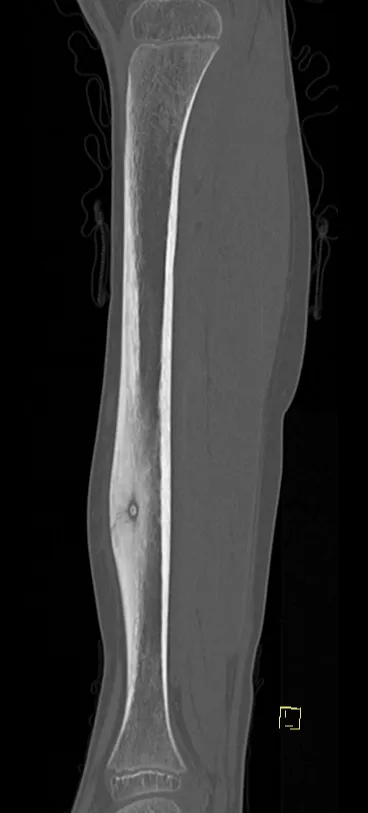

Browse 8 medical images tagged with benign. This collection includes various imaging modalities for medical education and reference.

- This collection contains 8 radiology images related to benign, including various imaging modalities such as X-rays, MRIs, CT scans, and ultrasound images commonly used in medical diagnosis and education.